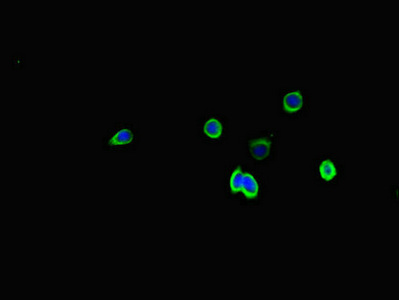

Immunofluorescent analysis of HepG2 cells using CSB-PA022725LA01HU at dilution of 1:100 and Alexa Fluor 488-congugated AffiniPure Goat Anti-Rabbit IgG(H+L)

Immunofluorescent analysis of PC-3 cells using CSB-PA022725LA01HU at dilution of 1:100 and Alexa Fluor 488-congugated AffiniPure Goat Anti-Rabbit IgG(H+L)